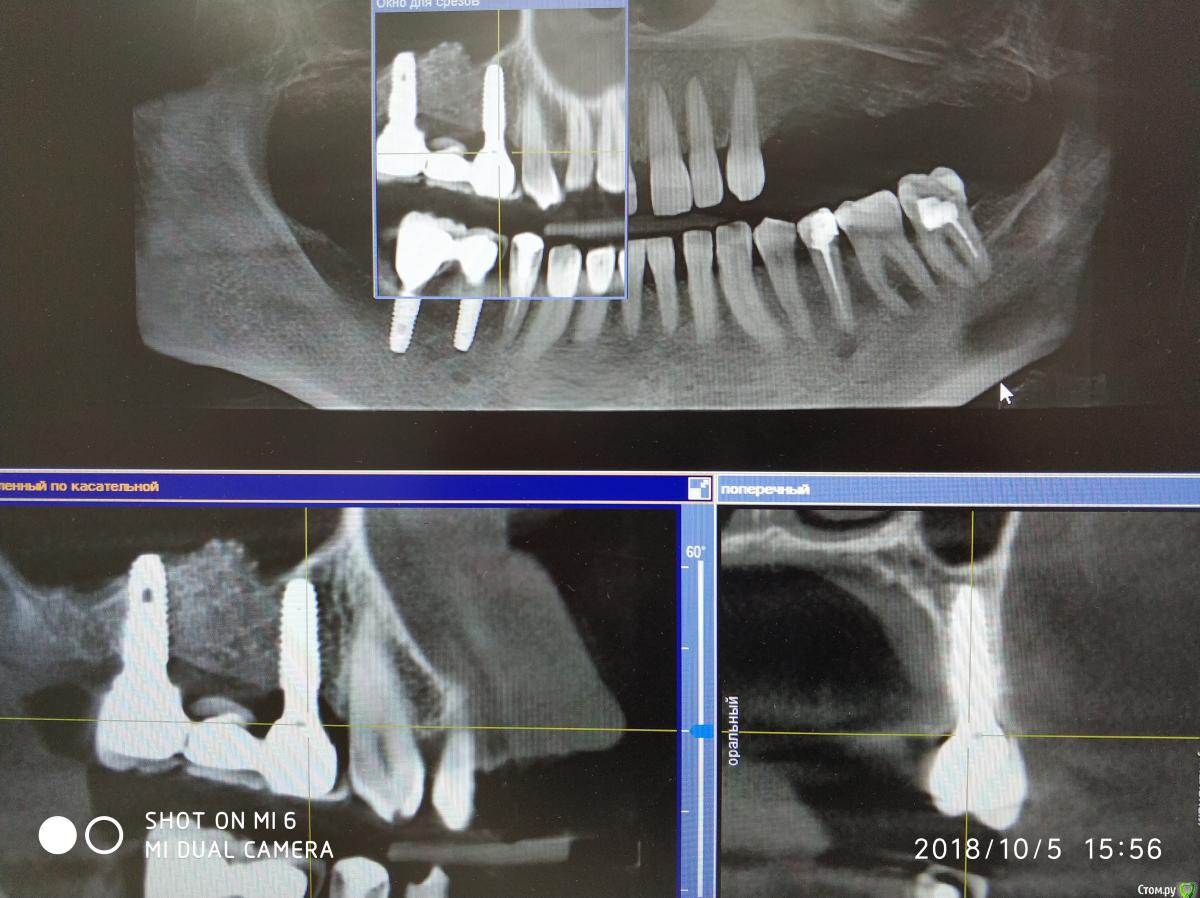

Nazim_NV86 Опубликовано 7 августа, 2018 Автор Поделиться Опубликовано 7 августа, 2018 14-16 с синусом стоят год, стоит металлокерамика. 45,46 пока с фдм. Осстем. Ссылка на комментарий

Nazim_NV86 Опубликовано 11 октября, 2018 Автор Поделиться Опубликовано 11 октября, 2018 Появилась свежая КЛКТ Ссылка на комментарий

Nazim_NV86 Опубликовано 12 октября, 2018 Автор Поделиться Опубликовано 12 октября, 2018 Срезы пазух. На чувствительность языка жалоб не слышал. Как приедет тесты сделаю. Ссылка на комментарий